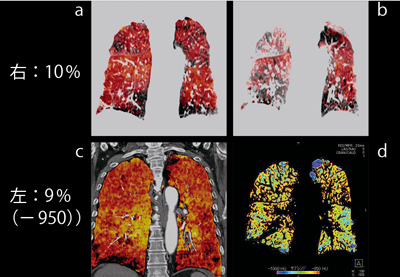

線維症と肺気腫が合併したcombined pulmobary fibrosis emphysema(CPFE)における,XeイメージとLung PBVの同時評価について述べる。CPFEは,parenchyma画像では赤い領域のなかにLAA(青)が散在し,Xeイメージ呼気で末梢までXeが残ることが特徴である。

●症例2:CPFE(図7)

単純CT(図7d)でもデンシティが高く,線維症であることがわかるが,parenchyma画像(図7b)でも線状の赤い表示が多数認められ,線維化が明瞭に認められる。また,Xeの欠損域(図7a,c)では血流が保たれており,肺気腫とは異なるCPFEの特徴が見て取れる。

図8に,症例2のコロナル画像を示す。

![]() 図7 症例2:CPFE(72歳,男性),下肺野,アキシャル画像 a:Xeイメージ b:parenchyma画像 c:Lung PBV d:単純CT画像 |

![]() 図8 症例2:CPFE(72歳,男性),コロナル画像 a:Xeイメージ(吸気) b:Xeイメージ(呼気) c:Lung PBV d:parenchyma画像 |

●CPFE評価のまとめ

症例の検討から,CPFEは,気腫肺の容量が肺気腫と比べて少ない傾向があり,XeイメージとLAAで乖離が見られることがある。また,肺気腫に比べて血流が保たれていると考えられる。